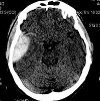

КТ черепа

Исследование излучения позволяет исследовать кости черепов мозга и лица, челюстей и лобных пазух, оценить целостность и симметрию твердых структур, выявить расхождение швов, определить размер и форму полостей. КТ черепа можно использовать при черепно-мозговой травме. Методика позволяет установить наличие, положение и характер перелома, подтвердить повреждение вещества мозга. Используя процедуру, они определяют причины ликвореи в случае перелома основания черепа, диагностируют патологию височной кости с возможным повреждением слухового аппарата, искривление перегородки носа, локализацию соответствующих зубов. Процедура показана для выявления опухолей костей черепа и околоносовых пазух (в том числе при росте опухолей из соседних областей), метастазов, полипов, кист. Техника предписана для исключения большего количества костных повреждений при фиброзной дисплазии, которая может протекать бессимптомно на ранних стадиях.

При использовании метода структуры мягких тканей видны хуже, чем кости, поэтому для их исследования иногда используют компьютерную томографию с контрастированием. Процедура проводится при ушибах, отеках лица и шеи, гематомах, воспалительных процессах, опухолях мягких тканей. В качестве показаний можно считать тяжелое течение лобного синусита, синусит при подозрении на распространение за пазухой с поражением мягких тканей и твердых структур. Кроме того, сканирование выполняется перед сложными реконструктивными операциями, чтобы заранее спланировать ход хирургического вмешательства (особенно пластики) и в послеоперационный период, чтобы оценить результаты операции.